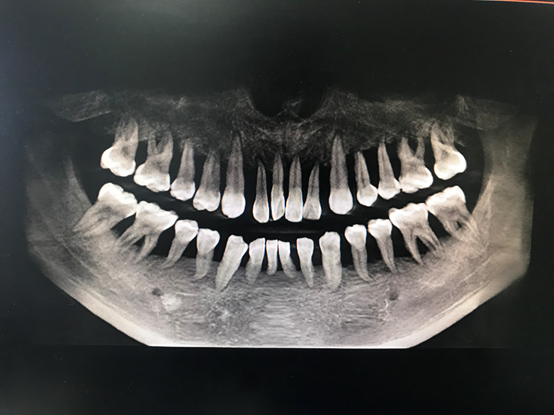

“我從醫(yī)這么多年也是第一次見到如此嚴(yán)重的牙周炎患者?!苯釉\醫(yī)生周矗說,從小周的口腔檢查中發(fā)現(xiàn),他的全口牙齒都有牙齦的膿腫,伴有嚴(yán)重的骨頭萎縮以及吸收,所有牙齒幾乎都是3度松動(dòng),并且口腔異味特別嚴(yán)重,牙齒上附著大量牙結(jié)石及食物軟垢。

近日,25歲的小周碰到了一個(gè)大難題,他的牙“出問題了”,全口牙齒無法咀嚼,除了流食以外什么也不能吃。杭州師范大學(xué)附屬醫(yī)院牙周病診療中心醫(yī)生發(fā)現(xiàn),小周的牙齒情況類似于80歲的老太太,全口牙齒幾乎都是松動(dòng)無法行使咀嚼功能。這意味著小周口內(nèi)牙齒幾乎都要拔除,全口牙沒有幾個(gè)能保留。